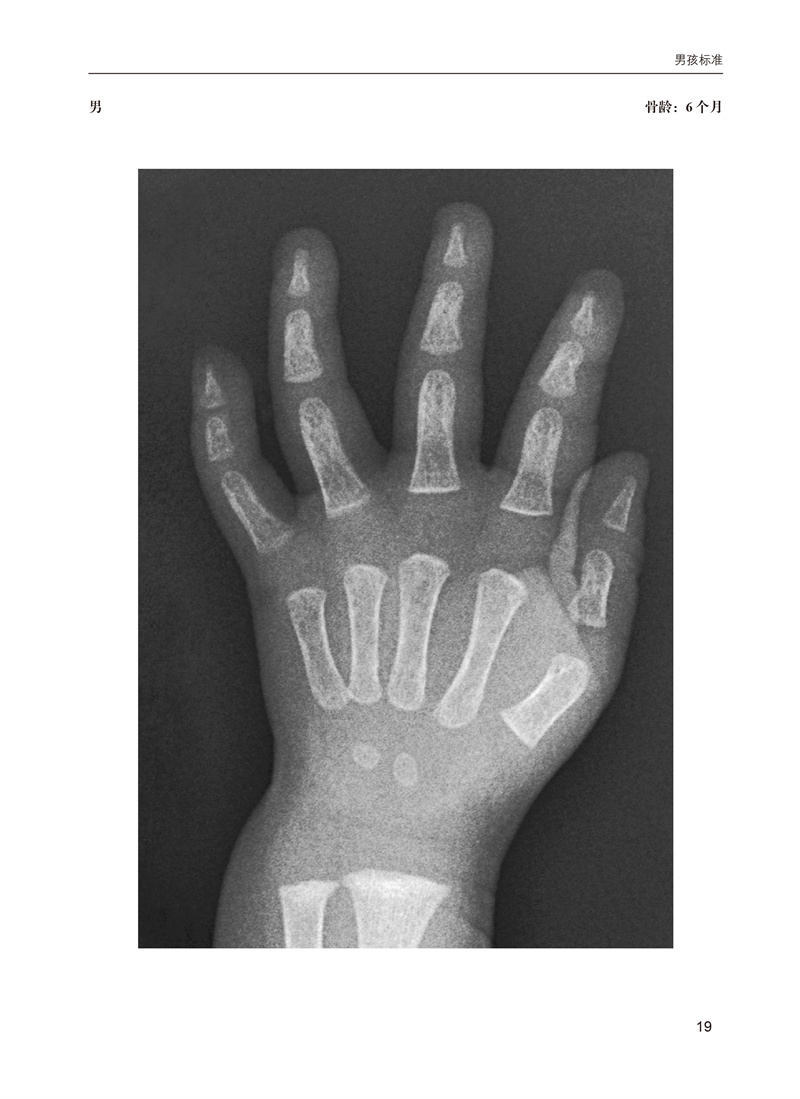

骨龄是国际公认的准确反应儿童生长发育的重要指标,也是临床医学、体育及法医学领域不可或缺的一项重要检查。本书基于广受欢迎的Greulich和Pyle图谱,将儿童骨骼成熟度的确定方法现代化。它提供了大量的图像,这些图像是从弗吉尼亚大学的PACS中的数千张数字X光片中精心挑选出来的,以最佳展示重要发育性骨特征,并按年龄和性别组织,以便快速参考。为了便于学习和临床图像分析,带注释和不带注释的图像成对出现,以便容易比较。图像上的简洁注释取代了冗长的文本,以提供更快速、更清晰的骨骼年龄标志。这些注释强调了重要而微妙的特征,帮助区分否则看起来相似的图像。本书分为两大部分:男性和女性各年龄段标准图谱。本书是一个高质量的左手腕X线片标准图谱,捕捉了Greulich和Pyle公认标准的重大和细微细节。鉴于骨龄应用的广泛性,手和腕部骨骼发育不仅旨在为实践和培训放射科医生提供参考,也适用于所有将骨龄研究作为实践一部分的人员。